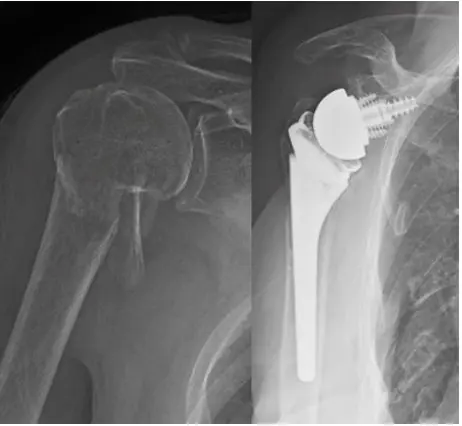

Total Shoulder Replacement – Before and After Images